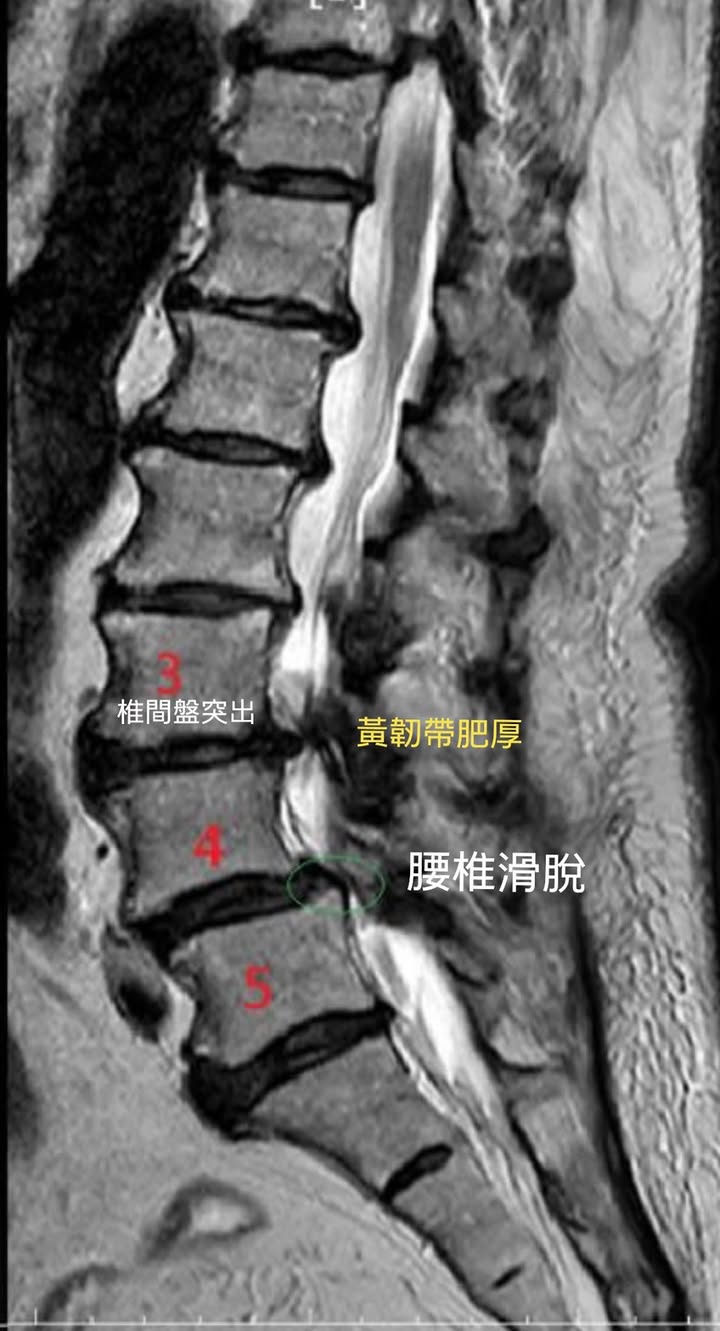

Cervical Spine Treatment Cases 腰椎治療案例 #巨大椎間盤突出一定要開刀嗎? #兩家醫學中心外科醫師說很嚴重! #有沒有辦法逆轉勝... 2021.08.10 ❖ 椎間盤突出治療醫案 ❖晨起痛爆整個人無法工作心情沮喪 😂骨科醫師說復健如果沒效可... 2022.05.12 #天才年輕賽車手巨大椎間盤突出醫案 #八周治療完全逆轉勝康復 #重新回到合法賽車場競... 2021.07.20 #腰椎滑脫痛苦不堪 #右腳麻痛無法彎腰刷牙 #感謝桃園市楊小姐熱情見證 #患者親自贈送... 2021.06.15 #巨大椎間盤突出醫案 #真的逆轉勝超感動 #三個月治療完全徹底改善 #脊刻救援成功 #徹... 2021.06.12 ⭕️L4L5巨大椎間盤突出治療醫案 🌟八週之內解除危機逆轉成功 😁順利降級成功解封印 💪... 2021.07.08 #腰椎多節椎管狹窄治療醫案 #腎臟病患者可接受中醫微創筋膜療嗎? #感謝台北市信義區張... 2021.06.01 #腰椎手術失敗綜合症候群 #感謝桃園呂伯伯熱情見證 #何時必須優先考慮再次動刀 #脊刻... 2021.07.31 #感謝新店吳先生熱情見證 #車禍後導致椎間盤突出醫案 #傳統復健六周無效痛苦不堪 #脊... 2021.05.29 #椎間盤突出治療醫案 #破紀錄三週解決 #真的逆轉勝 #感謝新莊周先生熱情見證 #脊椎整... 2021.05.26 #脊椎滑脫合併椎管狹窄醫案 #感謝台北市曹阿姨熱情見證 #之前大痛到無法走路只能拐杖... 2021.05.14 #嚴重椎管狹窄醫案導致寸步難行 #最嚴重走路無法超過十公尺 #疼痛到整個人憂鬱到不... 2021.05.07 #巨大椎間盤突出醫案逆轉勝 #感謝台北士林王先生熱情見證 #脊椎整合中醫微創療法 #原... 2021.04.29 #台灣越南國際醫療成功 #脊椎整合中醫微創療法逆轉勝 #腰椎椎間盤突出醫案 #曾經大痛... 2021.04.23 #椎間盤突出逆轉勝醫案 #原本骨科建議開刀 #脊刻救援成功 #感謝雲林患者陳小姐熱情見... 2021.04.09 ← 上一頁 7 8 9 10 11 下一頁 →